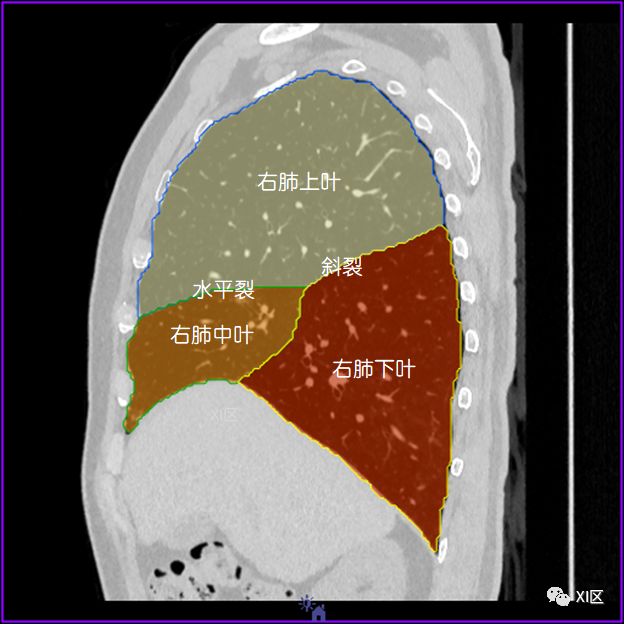

肺的分叶

左肺借斜裂成上、下两叶;右肺借斜裂和水平裂成上、中和下叶三叶。

矢状位